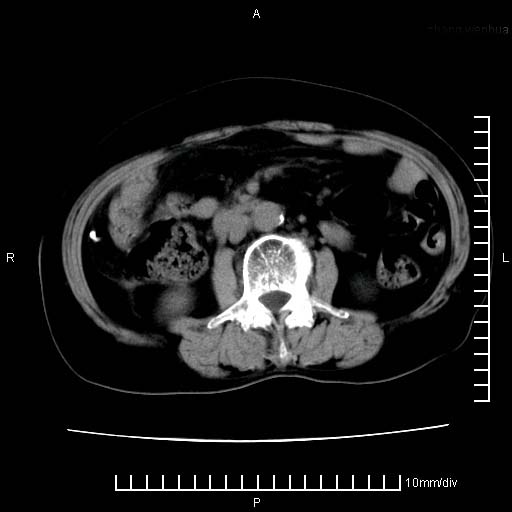

下腹疼痛2月,加重并呕吐2天,下腹压痛,反跳痛。白细胞1万2.

下腹至盆腔较大包块,与邻近肠管关系密切,下腹疼痛2月,加重并呕吐2天,下腹压痛,反跳痛。白细胞1万2.

由于没有做肠道准备很难分清是哪根肠管,但看位置考虑为升结肠回盲部的问题,我首先考虑化脓性阑尾炎,不除外结肠癌合并感染化脓。建议做增强进一步明确。

补充:道格拉斯腔内有积液,且密度较高,显然提示有感染。

考虑右侧卵巢囊肿伴感染可能性大。

附件实性肿块有坏死 考虑卵巢癌

来源于附件占位—多考虑:卵巢癌!